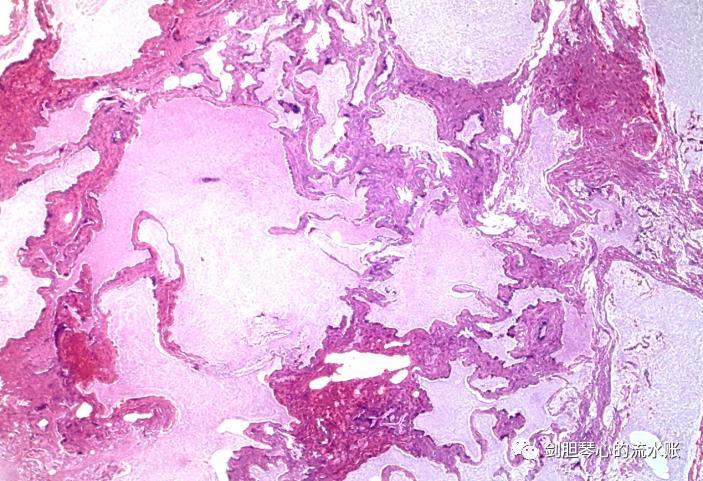

术中切除标本,快速冰冻病理切片显示:隔离肺。术后病理诊断:叶外型右膈下肝后隔离肺(叶外型)。镜下可见不规则的支气管、细支气管和肺泡,比正常人大2-5倍。

镜下可见不规则的支气管、细支气管和肺泡,比正常人大2-5倍